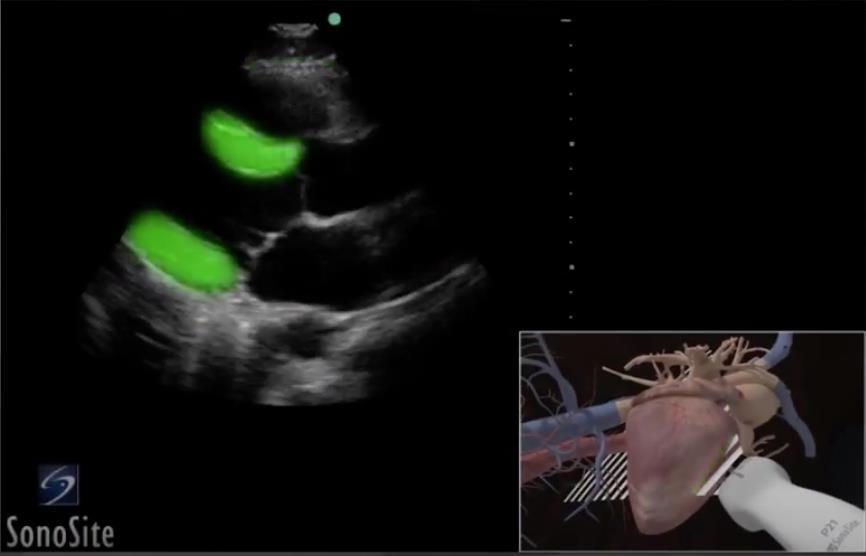

Heart Highlighted Myocardium Image

Highlighted Area: Myocardium